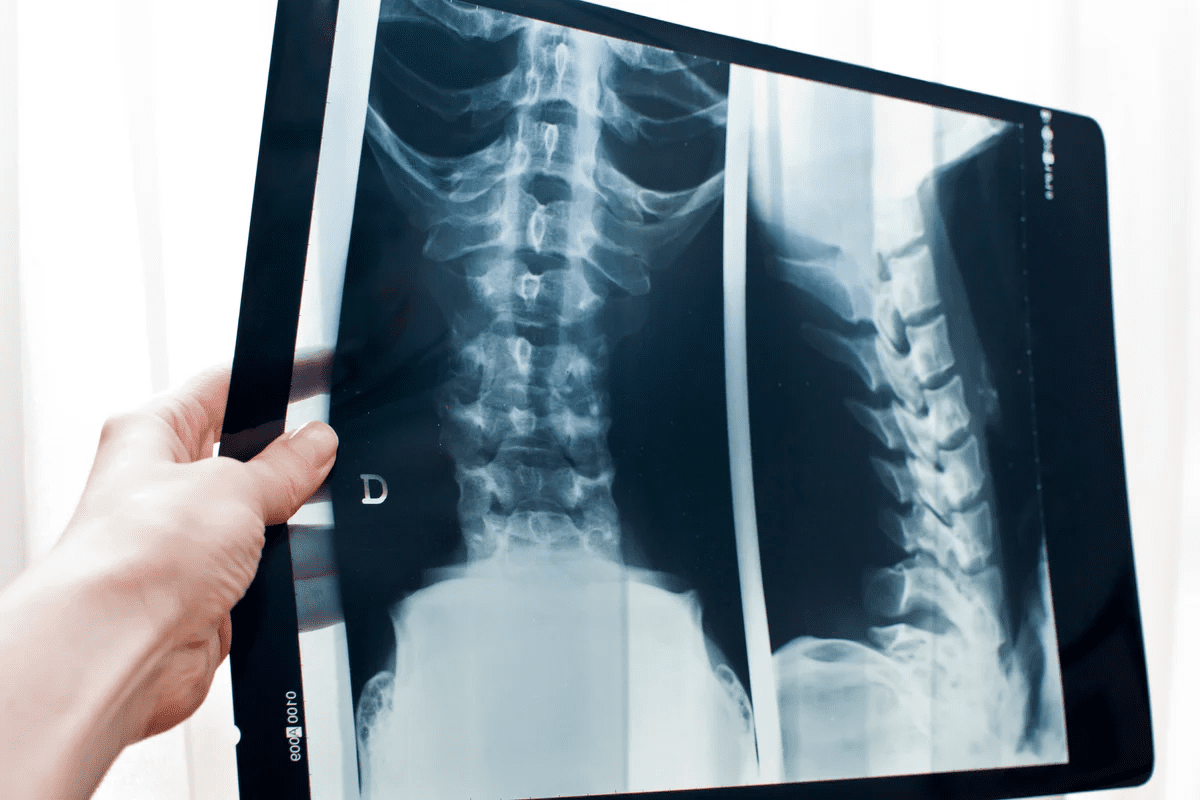

Imaging Studies for Confirming MI

While ECG and cardiac biomarkers are primary diagnostic tools, imaging studies can provide additional information to confirm the diagnosis and assess the extent of cardiac damage. Techniques such as echocardiography and cardiac magnetic resonance imaging (MRI) can visualize the heart’s structure and function, helping to identify areas of damaged myocardium.

These imaging modalities are particularly useful in cases where the diagnosis remains uncertain after initial testing or when assessing the long-term impact of an MI on cardiac function.